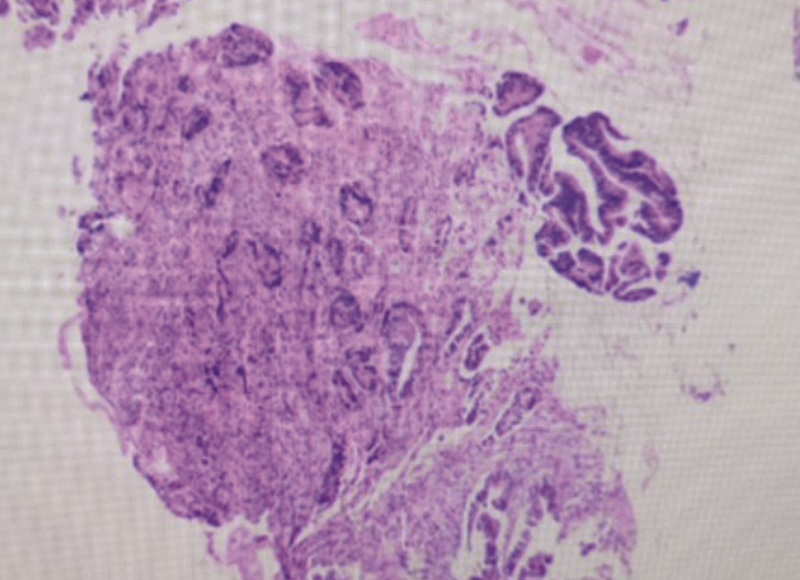

新辅助放化疗对局部晚期直肠癌(LARC)的肿瘤退缩、R0切除、局部控制率、器官保存率等方面均明显优于传统治疗模式,现已成为LARC的新标准治疗方案,但目前仍存在一些具有争议及未解决的问题。现报道1例LARC患者接受新辅助放化疗联合动脉栓塞灌注治疗后再行手术治疗并取得良好效果,这种新辅助治疗模式可供临床参考。